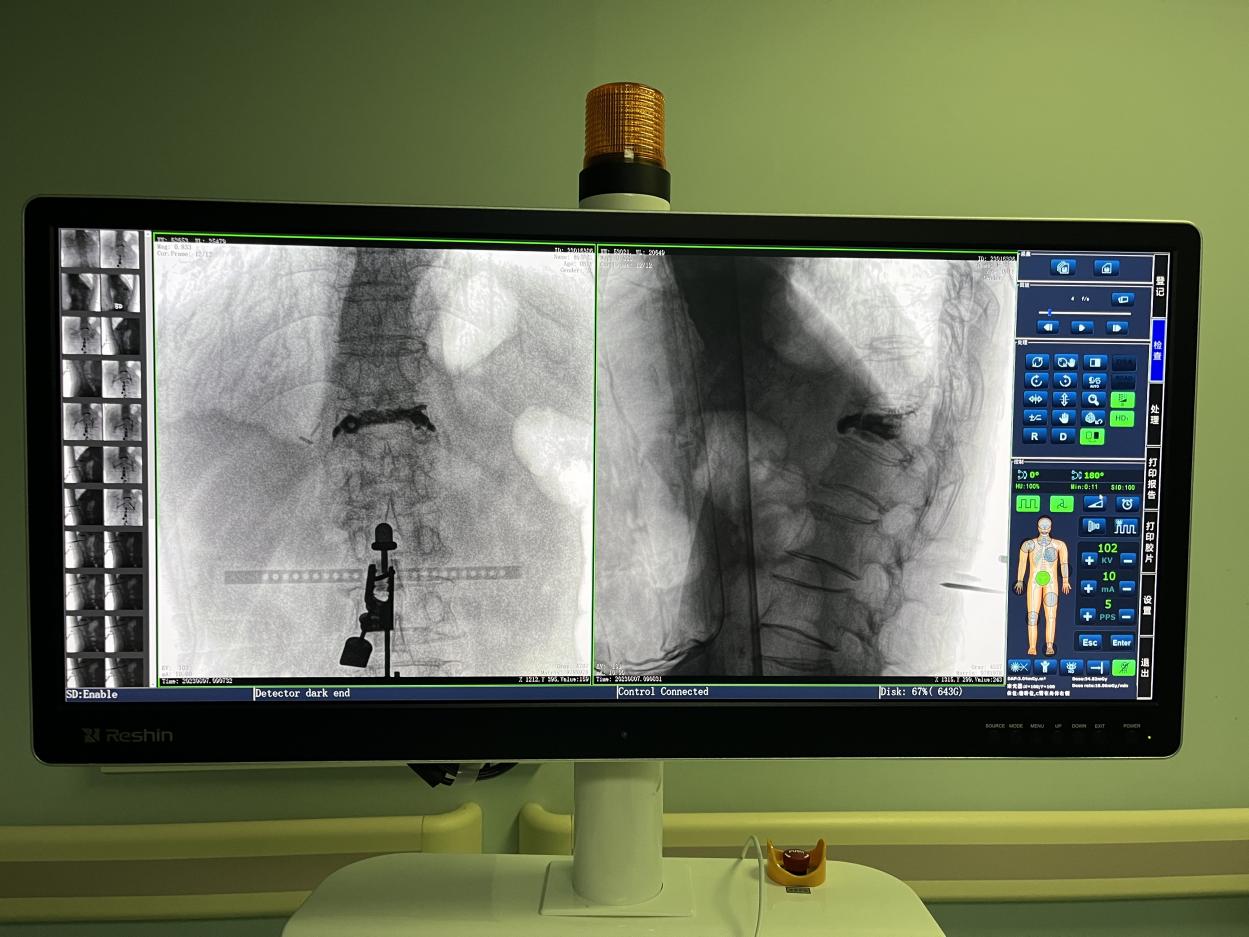

4.微創皮膚切口

傳統的開放式手術需暴露手術可見視野,以便醫生獲得更多的判斷信息,手術創口大,術后恢復時間長。而在骨科機器人輔助的微創手術中,手術創口僅為1~2厘米左右的小切口,創傷小、恢復快。

骨科機器人手術-術后影像